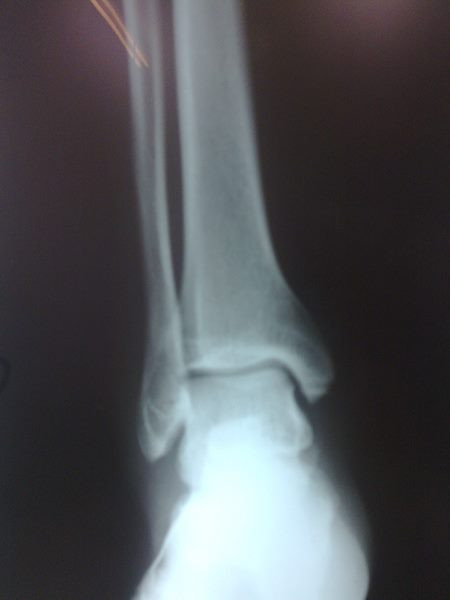

Radiografías con enfoque en fisiatría

Envíado por Dr. Hernán Darío Sánchez Ramos